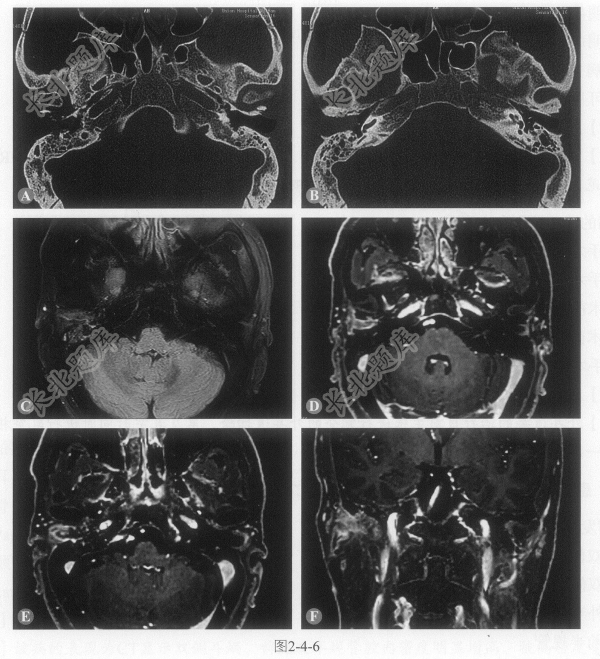

患者男性,50岁,右侧外耳道间断流水半年,伴耳痛、耳闷,无听力下降,右侧枕部头痛,无眩晕。CT和MRI图像如图2-4-6。

- 多项选择题1.该病的影像表现有:

A、外耳道前壁骨质破坏

B、外耳道后壁骨质破坏

C、锤骨骨质破坏

D、外耳道肿块T

WI明显强化E、伴发右侧乳突炎症

- 多项选择题2.该病最有可能的诊断是:

A、坏死性外耳道炎

B、外耳道胆脂瘤

C、外耳道癌

D、外耳道黑色素瘤

E、外耳道疖肿

- 多项选择题3.有关本病MRI检查的说法正确的是:

A、明确病变的范围

B、明确是否侵犯颅内

C、明确有无淋巴结转移

D、病变强化明显

E、可显示腮腺内淋巴结增大